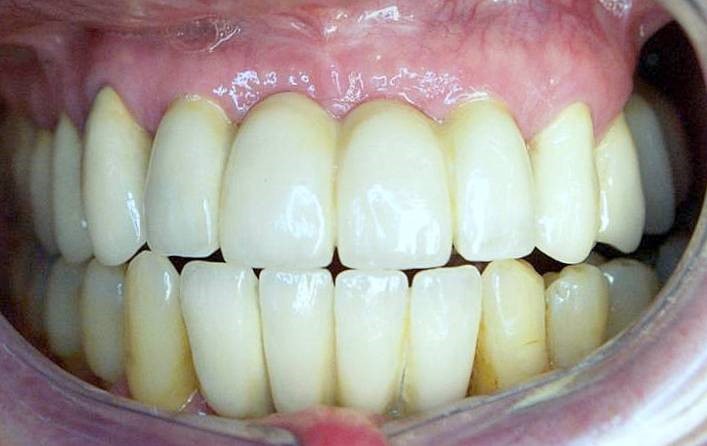

На фото представлены все этапы имплантации зубов от исходного состояния пациента до конечного результата.

На фото обычный случай замены одного зуба имплантатом, а также решение в случае беззубой челюсти или челюсти, пораженной пародонтозом.

Имплантация в стоматологии «Аркобалено» при пародонтозе зубов, представлены все этапы имплантации под ключ.